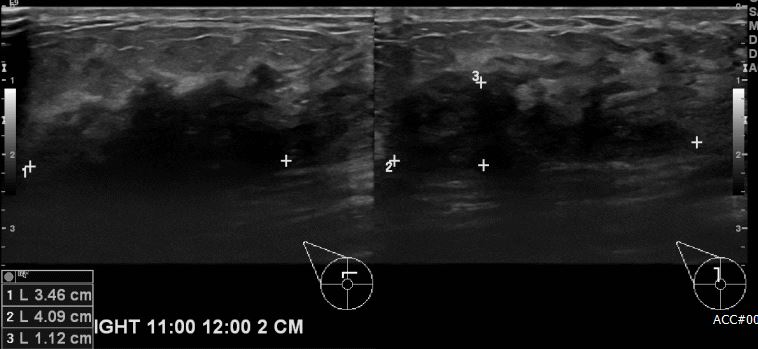

상기환자 우측 유방에 멍울로 내원하신 60대 여성분으로 우측 유방 11시~12시 방향에서

2cm 떨어진 거리의 멍울 조직검사 시행하여 우측 유관암 진단 되었습니다.